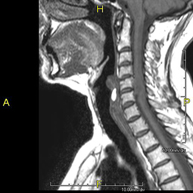

- Cervical spine MRI

This non-invasive diagnostic procedure uses an electromagnetic field and radio waves (from a transmitter and receiver) to acquire high-definition anatomical images of the cervical spine. It is a radiation-free procedure. Indicated for: trauma, spinal degeneration, hernias.